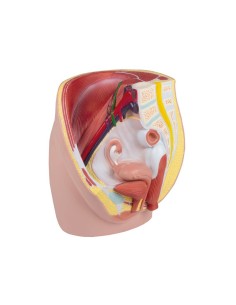

Dal cranio in 22 parti con incastri magnetici ai modelli di colonna vertebrale, da quelli di articolazioni a quelli di cuore, ogni pezzo della nostra collezione è progettato per un’immersione totale nello studio dell’anatomia umana. I nostri modelli, realizzati tramite scansioni di ossa vere, garantiscono un’esperienza tattile autentica e una fedeltà di peso quasi identica agli originali.

Essenziali per studenti e professionisti, i nostri modelli anatomici sono strumenti didattici che permettono di osservare le strutture anatomiche con precisione, eliminando la necessità di dissezioni o studi invasivi. Sono inoltre utili per spiegare ai pazienti le patologie, rendendo la comunicazione più efficace e risparmiando tempo prezioso.